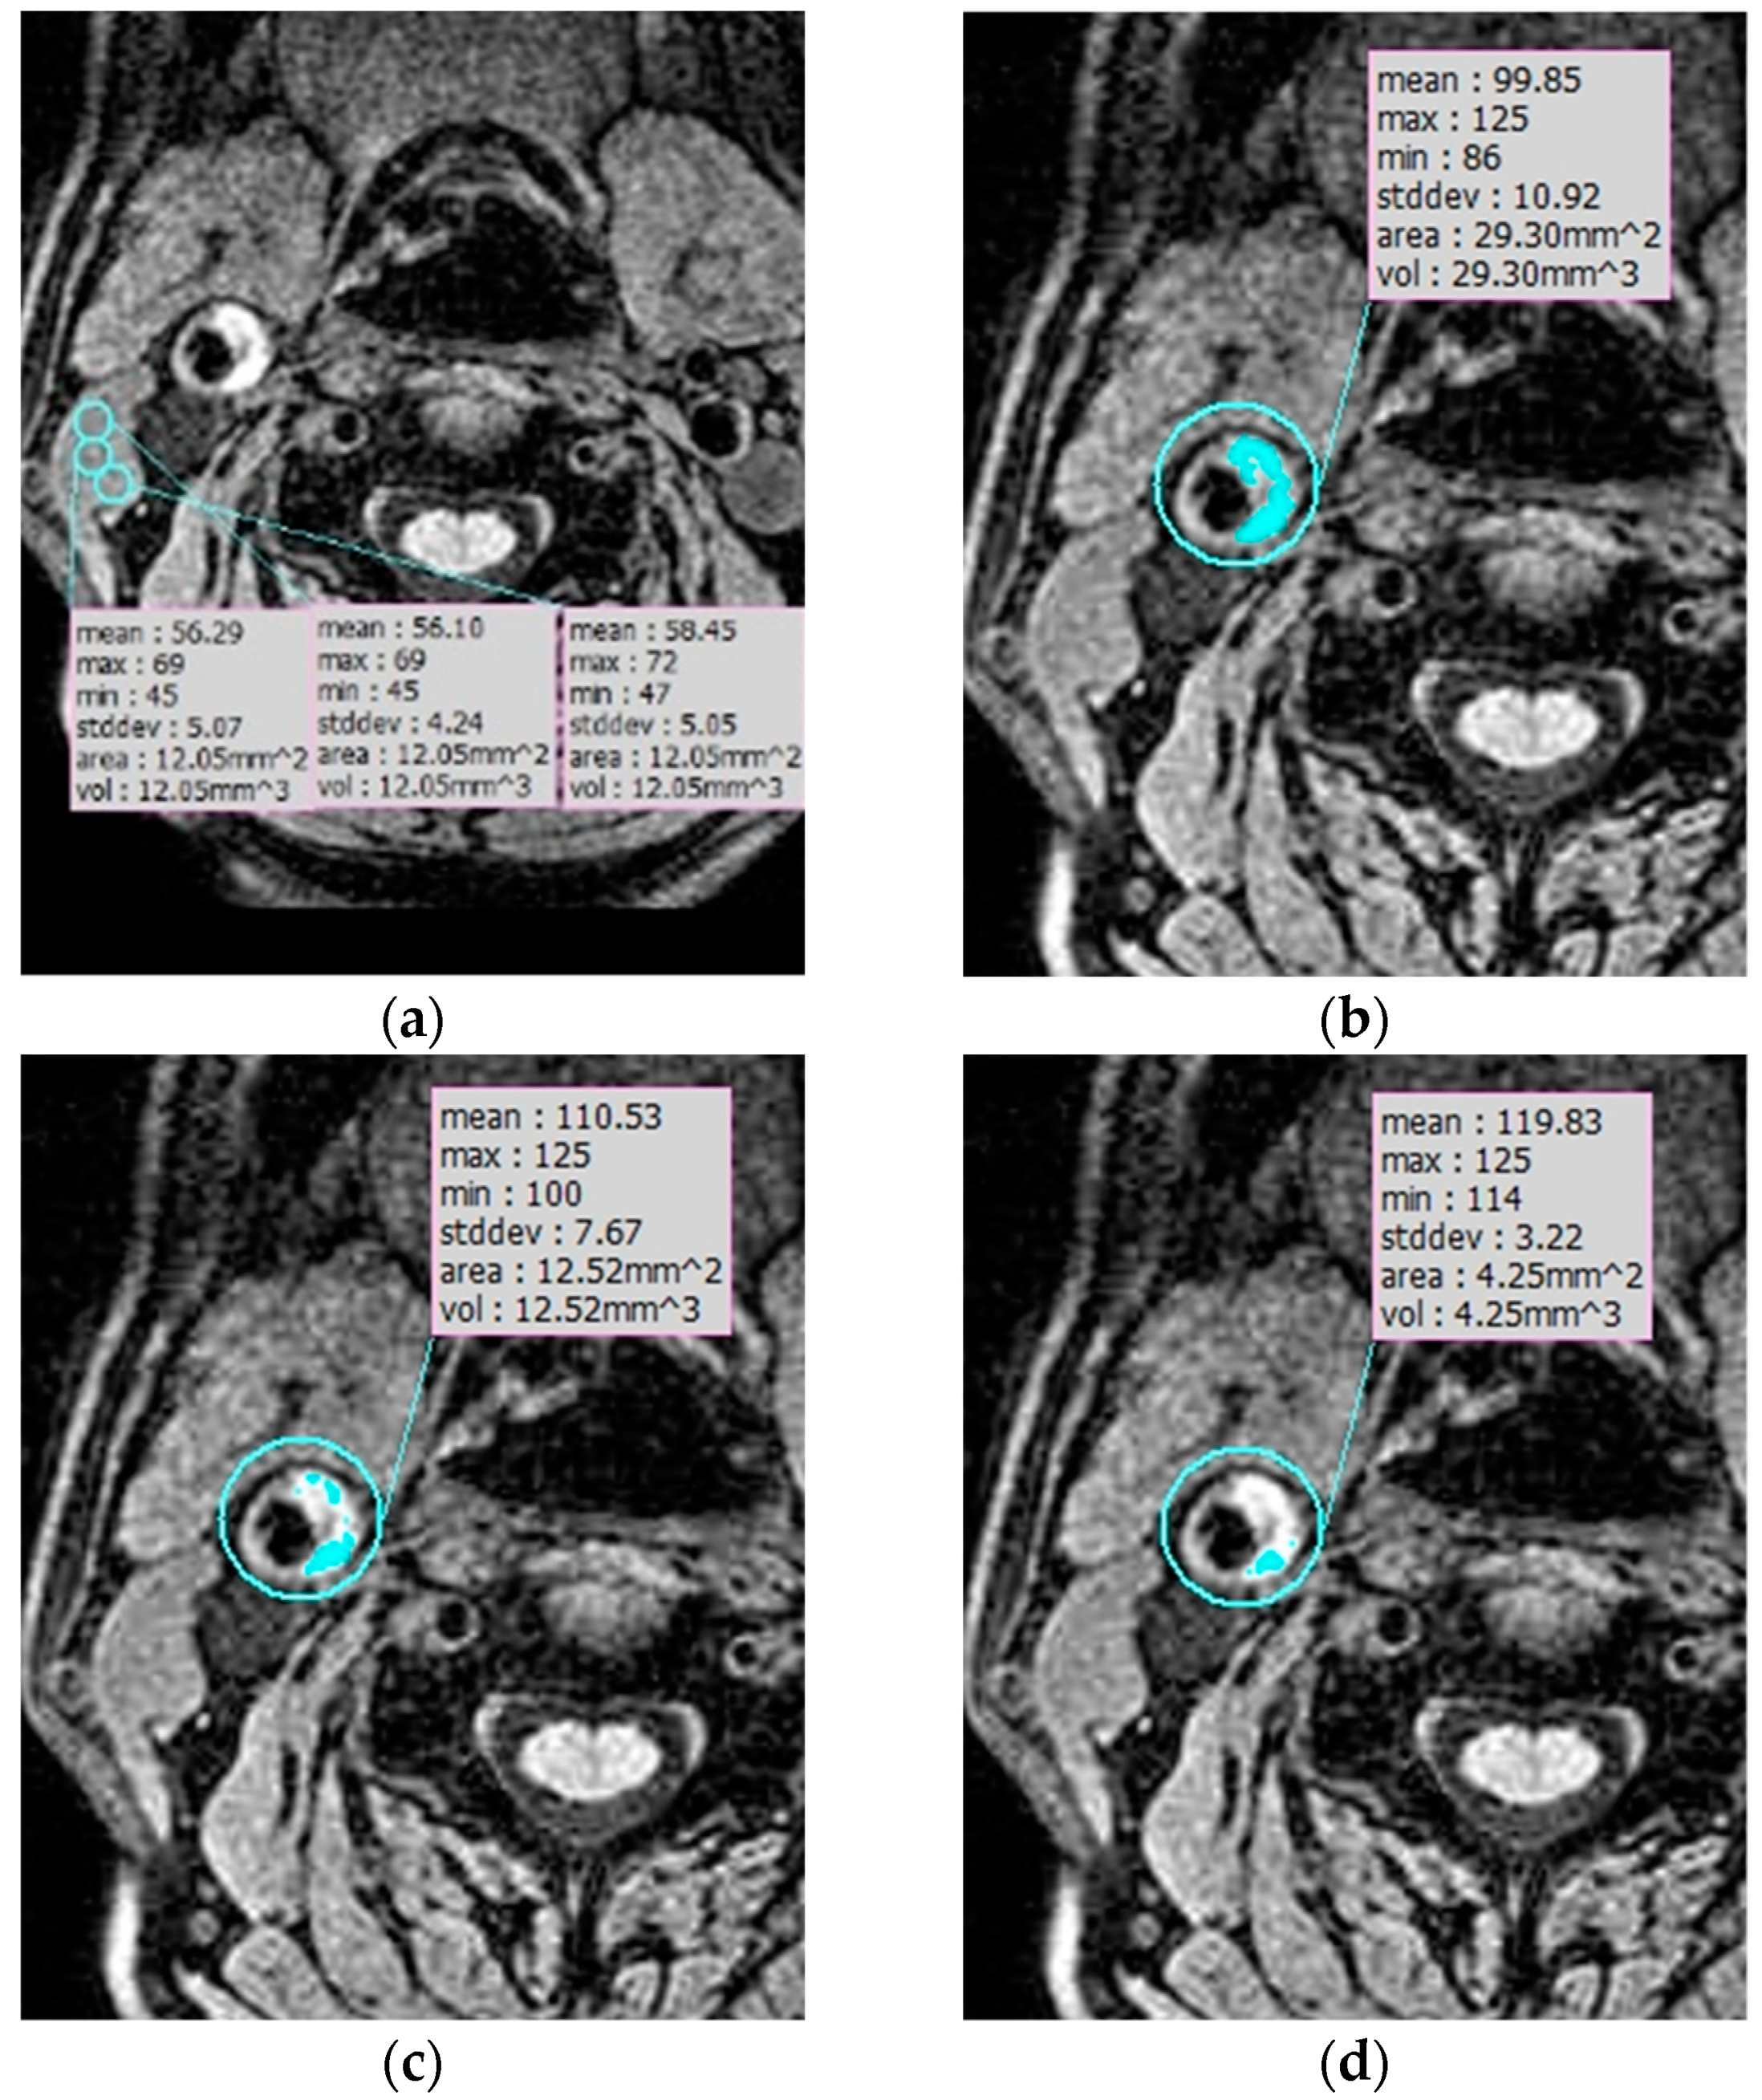

- Liu, J.; Balu, N.; Hippe, D.S.; Ferguson, M.S.; Martinez-Malo, V.; DeMarco, J.K.; Zhu, D.C.; Ota, H.; Sun, J.; Xu, D.; et al. Semi-automatic carotid intraplaque hemorrhage detection and quantification on Magnetization-Prepared Rapid Acquisition Gradient-Echo (MP-RAGE) with optimized threshold selection. J. Cardiovasc. Magn. Reson. 2016, 18, 41. [Google Scholar] [CrossRef] [PubMed]